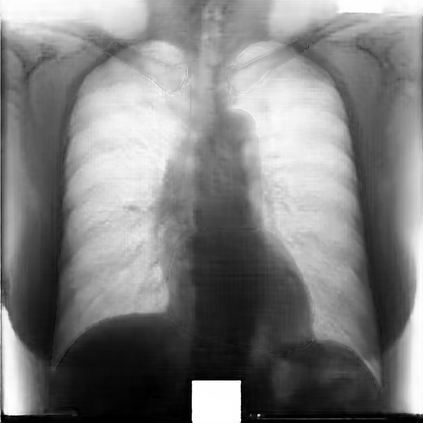

Multi-organ segmentation of X-ray images is of fundamental importance for computer aided diagnosis systems. However, the most advanced semantic segmentation methods rely on deep learning and require a huge amount of labeled images, which are rarely available due to both the high cost of human resources and the time required for labeling. In this paper, we present a novel multi-stage generation algorithm based on Generative Adversarial Networks (GANs) that can produce synthetic images along with their semantic labels and can be used for data augmentation. The main feature of the method is that, unlike other approaches, generation occurs in several stages, which simplifies the procedure and allows it to be used on very small datasets. The method has been evaluated on the segmentation of chest radiographic images, showing promising results. The multistage approach achieves state-of-the-art and, when very few images are used to train the GANs, outperforms the corresponding single-stage approach.